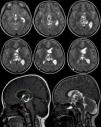

Teratoma is a common form of germ cell tumors composed of multiple tissues foreign to the site in which arise with a histological representation of all three germ cell layers. Intracranial teratomas are very rare. In this study, we report three cases of intracranial teratomas with an interesting clinical course, neuroradiology, and outcome. In addition, we review the literature and convey important messages to the neuroscience community regarding issues related to the management of these rare tumors. The present cases are interesting examples of intracranial teratoma in terms of location of the tumor and neuroimaging findings. Delay in surgical intervention may complicate the course of the disease with progressive enlargement of tumors and development of complication including hydrocephalus. Using endoscopic surgical techniques may emerge as the preferred intervention option as compared to other traditional methods. We recommend the establishment of a national and international registry for intracranial tumors.